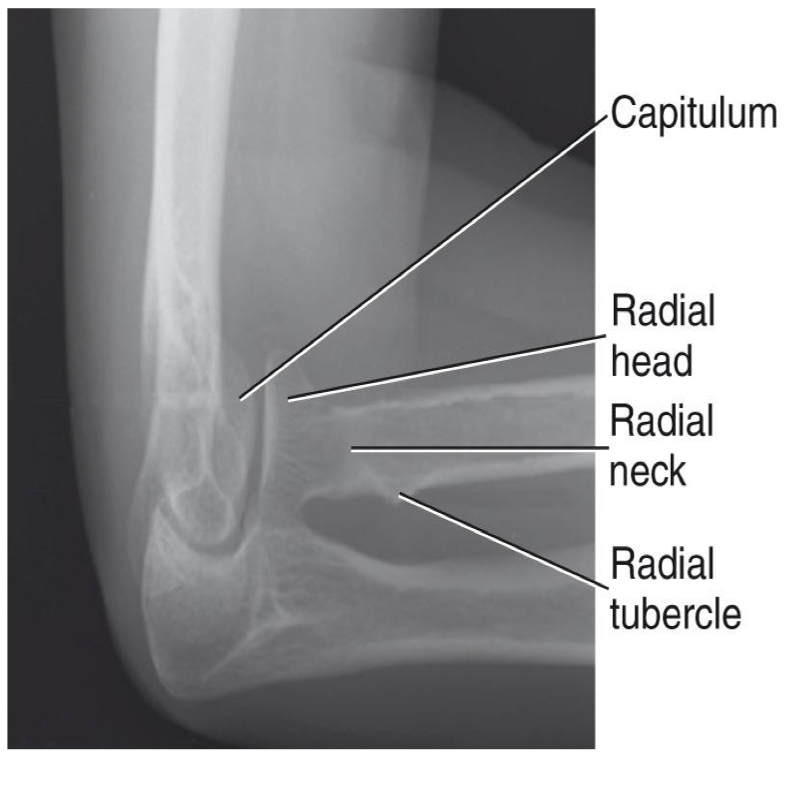

Lateral Elbow- Radial Head - Four Position Method

• Patient position

o Same as lateral elbow

• Four images acquired ( all on the same IR if possible) to show entire circumference of radial head

• Hand positions

supinated (maximum external location)

Lateral

3. Pronated

4. Internal rotation

Axial Lateral Elbow- Radial Head Coyle Method

• Patient and part positioned as for a lateral elbow

• Hand is pronated NOT lateral

• CR 45° toward the shoulder

• For radial head

• Useful in trauma and when patient cannot oblique elbow

Evaluation Criteria for radial head

• Open joint space between radial head & capitulum

• Radial head, neck & tuberosity nearly free of superimposition

• Radial tuberosity facing posterior (indicating the hand is pronated)

• Humeral epicondyles will be distorted due to the CR angle